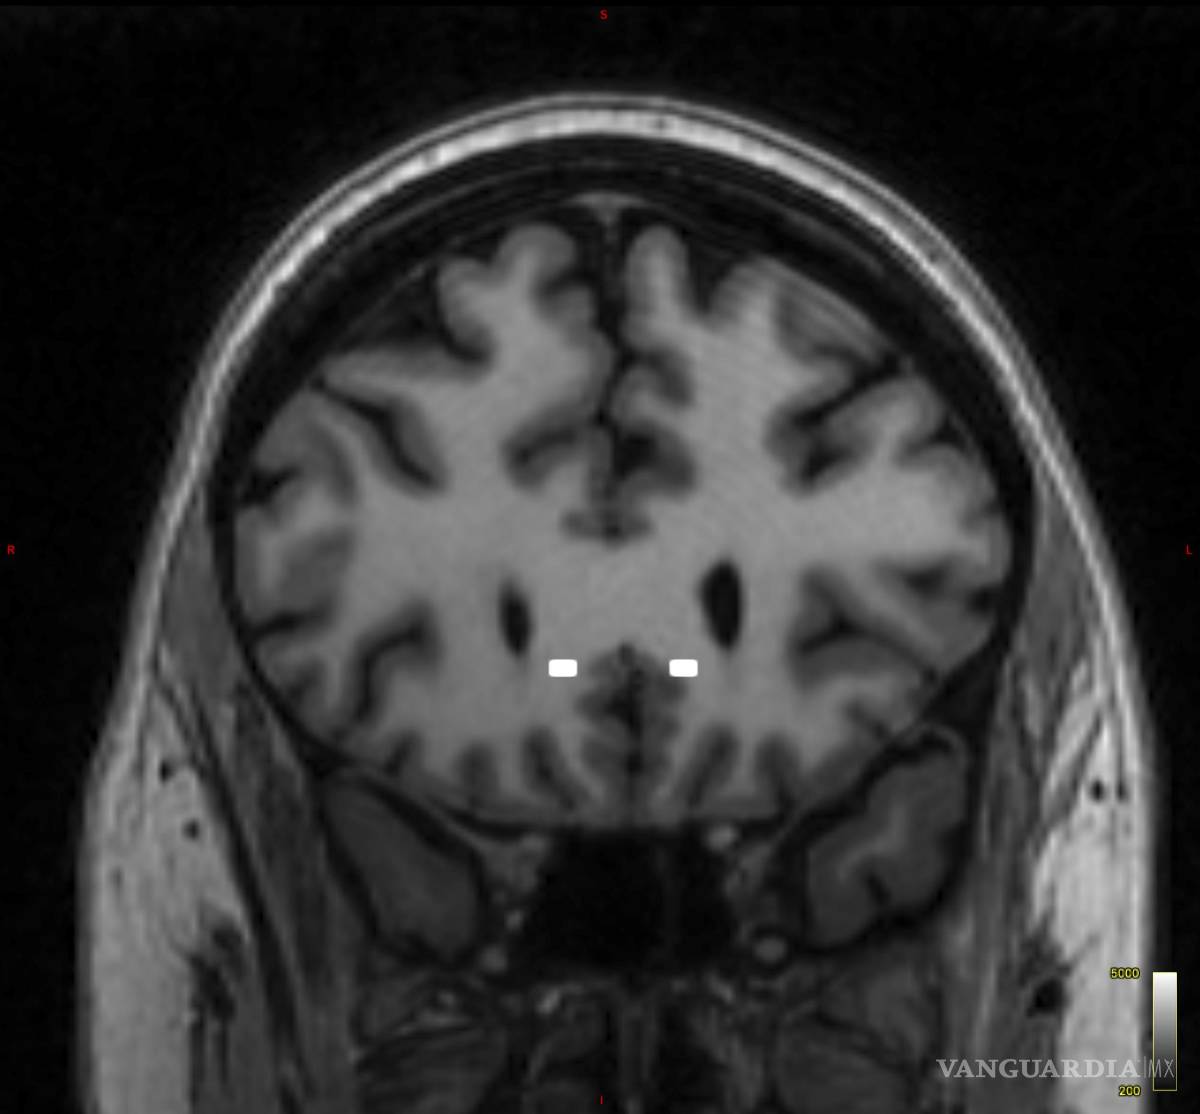

$!Imagen de escaneo cerebral que muestra los sitios seleccionados para los electrodos implantados en la paciente Emily Hollenbeck.

Hollenbeck se sometió a la cirugía cerebral bajo un sedante, pero despierta. El doctor Brian Kopell, que dirige el Centro de Neuromodulación de Mount Sinai, le colocó unos delgados electrodos metálicos en una región del cerebro llamada corteza cingulada subcallosa, que regula el comportamiento emocional y está implicada en los sentimientos de tristeza.

En la actualidad, los tratamientos en los que varios equipos efectúan pruebas tienen un diseño mucho más personalizado según el caso. El equipo de Mount Sinai es uno de los más destacados de Estados Unidos en la investigación de la ECP para la depresión. Allí, un experto en imágenes neurológicas utiliza imágenes cerebrales para localizar el punto exacto en el que Kopell debe colocar los electrodos.

Tenemos una plantilla, un plano de dónde vamos a ir exactamente”, dijo Mayberg, pionera en la investigación de la ECP y directora fundadora del Centro Familiar Nash para Terapéutica de Circuitos Avanzados de Mount Sinai. “El cerebro de cada persona es un poco distinto a los otros, al igual que los ojos de la gente están un poco más separados o una nariz es un poco más grande o más pequeña”.